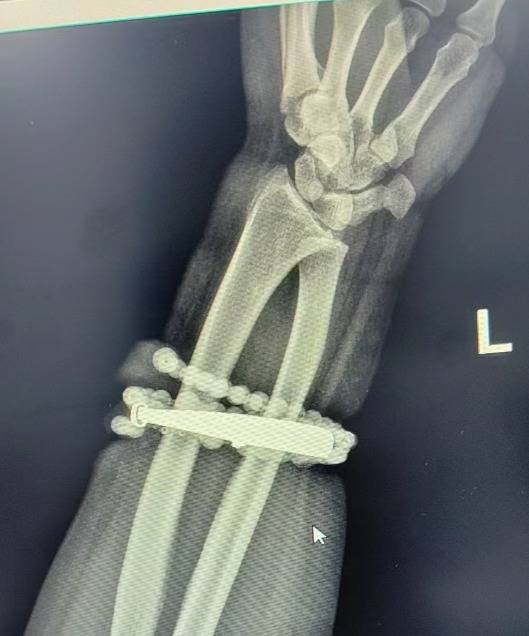

r然而创牛配资,就在两周前,龚女士的情况急转直下:手腕不仅疼痛加剧,还出现了明显的红肿,甚至有脓液渗出。她这才惊觉——手镯和串珠,已经有一部分“长”进了肉里,根本取不下来了!

r“这是典型的首饰长期压迫、摩擦,加上细菌感染,引发的慢性炎症和肉芽组织增生。”医生介绍,此时,手镯和串珠已经成了一个不断刺激皮肤、污染伤口的“病灶”,如果不尽快手术取出,感染可能进一步扩散,甚至危及生命或影响手臂功能。

经过一个多小时的手术,医生们将手镯和串珠从厚厚的增生组织中完整剥离出来。目前,龚女士恢复良好,已顺利出院。